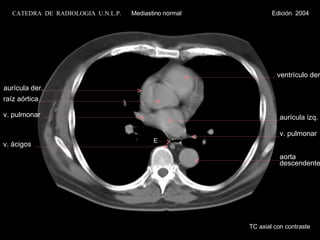

E ventrículo der. aurícula izq. v. pulmonar aurícula der. raíz aórtica v. pulmonar v. ácigos TC axial con contraste aorta descendente CATEDRA  DE  RADIOLOGIA  U.N.L.P.   Mediastino normal  Edición  2004

E ventrículo der.aurícula izq. v. pulmonar aurícula der. raíz aórtica v. pulmonar v. ácigos TC axial con contraste aorta descendente CATEDRA DE RADIOLOGIA U.N.L.P. Mediastino normal Edición 2004